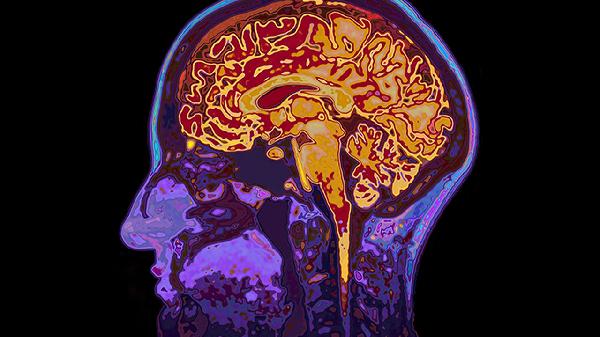

遲發(fā)性顱內(nèi)血腫可能由外傷后血管損傷、凝血功能障礙、高血壓、腦血管畸形、抗凝藥物使用等原因引起,可通過(guò)影像學(xué)監(jiān)測(cè)、藥物調(diào)整、手術(shù)清除血腫、控制血壓、糾正凝血功能等方式治療。

長(zhǎng)期高血壓可導(dǎo)致腦內(nèi)小動(dòng)脈玻璃樣變,血壓驟升時(shí)血管破裂出血。患者多有高血壓病史,突發(fā)劇烈頭痛伴嘔吐。急性期需靜脈用降壓藥物將血壓控制在安全范圍,后期需長(zhǎng)期服用降壓藥維持。

動(dòng)靜脈畸形、海綿狀血管瘤等血管結(jié)構(gòu)異常,在外力或血壓波動(dòng)時(shí)易破裂出血。常見(jiàn)于青壯年,突發(fā)神經(jīng)功能缺損癥狀。確診需腦血管造影,治療方式包括手術(shù)切除、介入栓塞或立體定向放療。